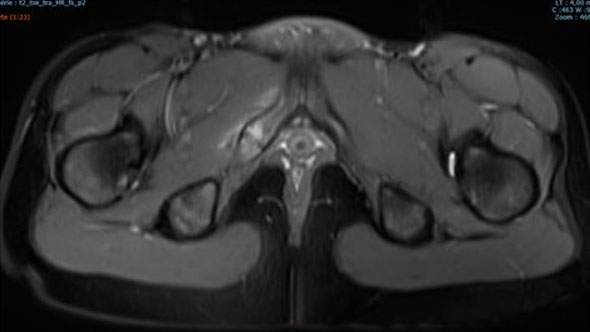

As described in the Wait et al. study [5], pelvic MRI performed on a whole-body 1.5 T scanner revealed hyperintense signal alteration of the bone marrow surrounding the right IPS on T2-weighted images, symmetrical enlargement of IPS, a transverse hypersignal band-like structure perpendicular to the pubic axis, a local collection, and marked edema of the surrounding soft tissues (Figure 4). These imaging findings, combined with clinical symptoms, were suggestive of acute osteomyelitis.

Figure 4: Pelvic MRI performed on a whole-body 1.5 T scanner reveals hyperintense signal alteration of the bone marrow surrounding the right ischiopubic synchondrosis on T2-weighted images, with symmetrical enlargement of the IPS. Additional findings include a transversal hypersignal band-like structure perpendicular to the pubic axis at the center of the right synchondrosis, a local collection, and marked edema of the surrounding soft tissues.

Share Image: